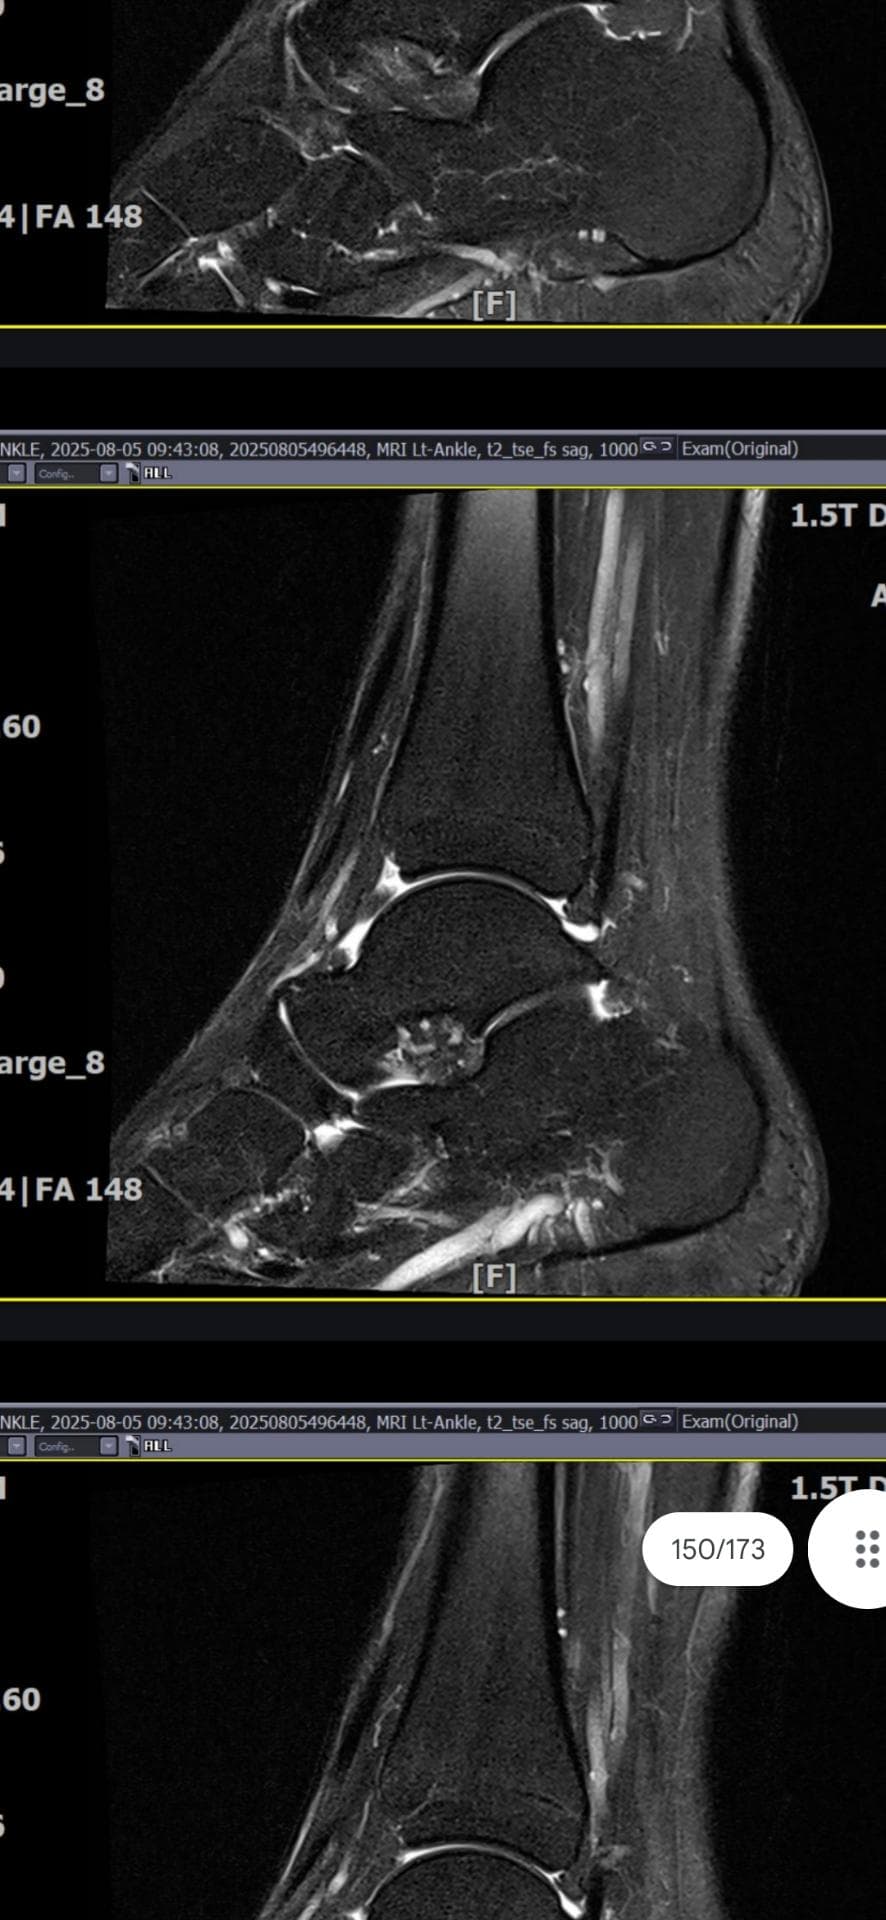

그래도 통증이 남아 8월 5일에 MRI를 촬영했는데, 병원에서는 “인대는 이어져 있고, 이 정도면 재활운동으로 호전될 것”이라는 설명을 들었습니다.

MRI 상 전거비인대와 발목 상태가 정말 회복 단계인지, 아니면 만성으로 넘어가는 건 아닌지 전문가분들의

의견을 듣고 싶습니다.

올려주신 mri를 보면 전거비인대는 연속성이 유지되고 있고 파열이나 큰 손상 흔적은 없어 재활로 회복 가능한 상태로 보입니다 다만 3개월 가까이 활동 시 통증과 미열감이 남아 있는 것은 조직 회복이 아직 완전히 끝나지 않았거나 주변 연부조직 관절 움직임 제한 등으로 인한 과민 반응일 수 있습니다.

초음파와 비교하면 mri 상으로 인대 연속성이 확인되므로 심각한 악화나 재파열은 아닌 것으로 판단됩니다